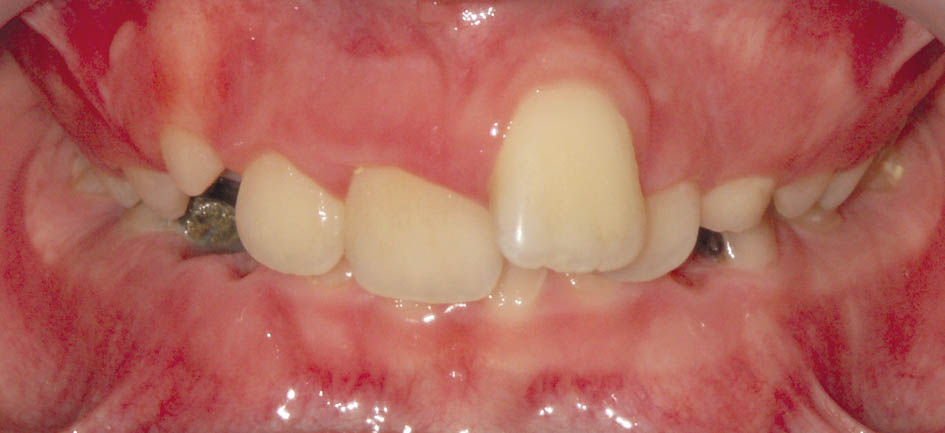

گاهی بیمار شما Div2 است و بخاطر رترودشدن انسیزورهای بالا و دیپبایت شدن بیمار دیگر اورجت ندارید. بیمار مندیبل را در زمان تهیه موم باید جلو بیاورد و چون اورجت ندارید این کار عملی نیست، لذا باید ابتدا اورجت بسازید و بعد موم بایت بگیرید (شکل 72-5 و 73-5).

شکل 72-5: بیمار کلاسII و دیپ بایت است.

شکل 73-5: نمای روبروی بیمار